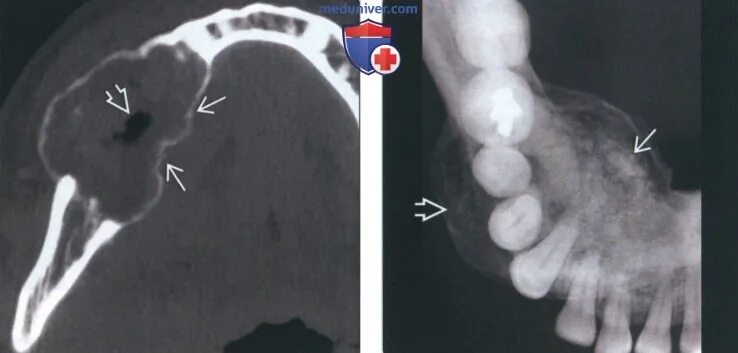

Фиброма кт